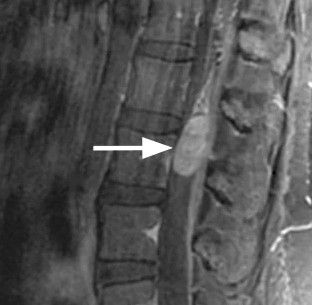

Até 10% dos pacientes com câncer podem desenvolver um quadro de compressão medular, sendo que em alguns casos, os sintomas decorrentes da compressão medular são os primeiros a se manifestarem. O segmento da coluna mais acometido pela compressão medular é o torácico, seguido pela região cervical e então pela região lombar e sacral.

O Diagnóstico é realizado com base na história clínica e exame físico completo, em associação com exames complementares específicos e estadiamento tumoral, quando pode-se lançar mão de exames de imagem como radiografias, tomografia computadorizada, ressonância nuclear magnética e cintilografia, além de exames laboratoriais diversos.